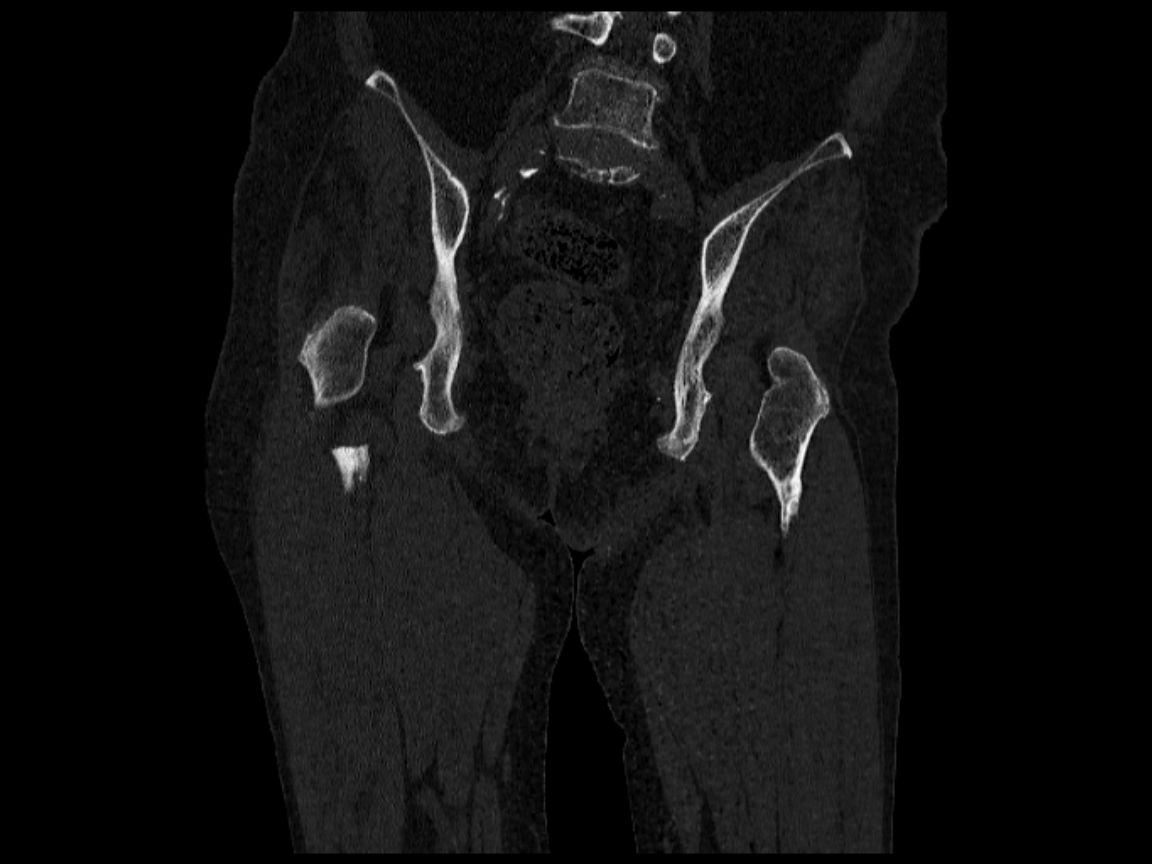

1. Q1:両側股関節-大腿骨単純X線写真(図1),単純CT(図2)の画像所見は?

図2 両側股関節-大腿骨単純CT(冠状断)

A)右大腿骨,B)左大腿骨

誌面掲載画像は,A)赤枠 B)青枠で示す